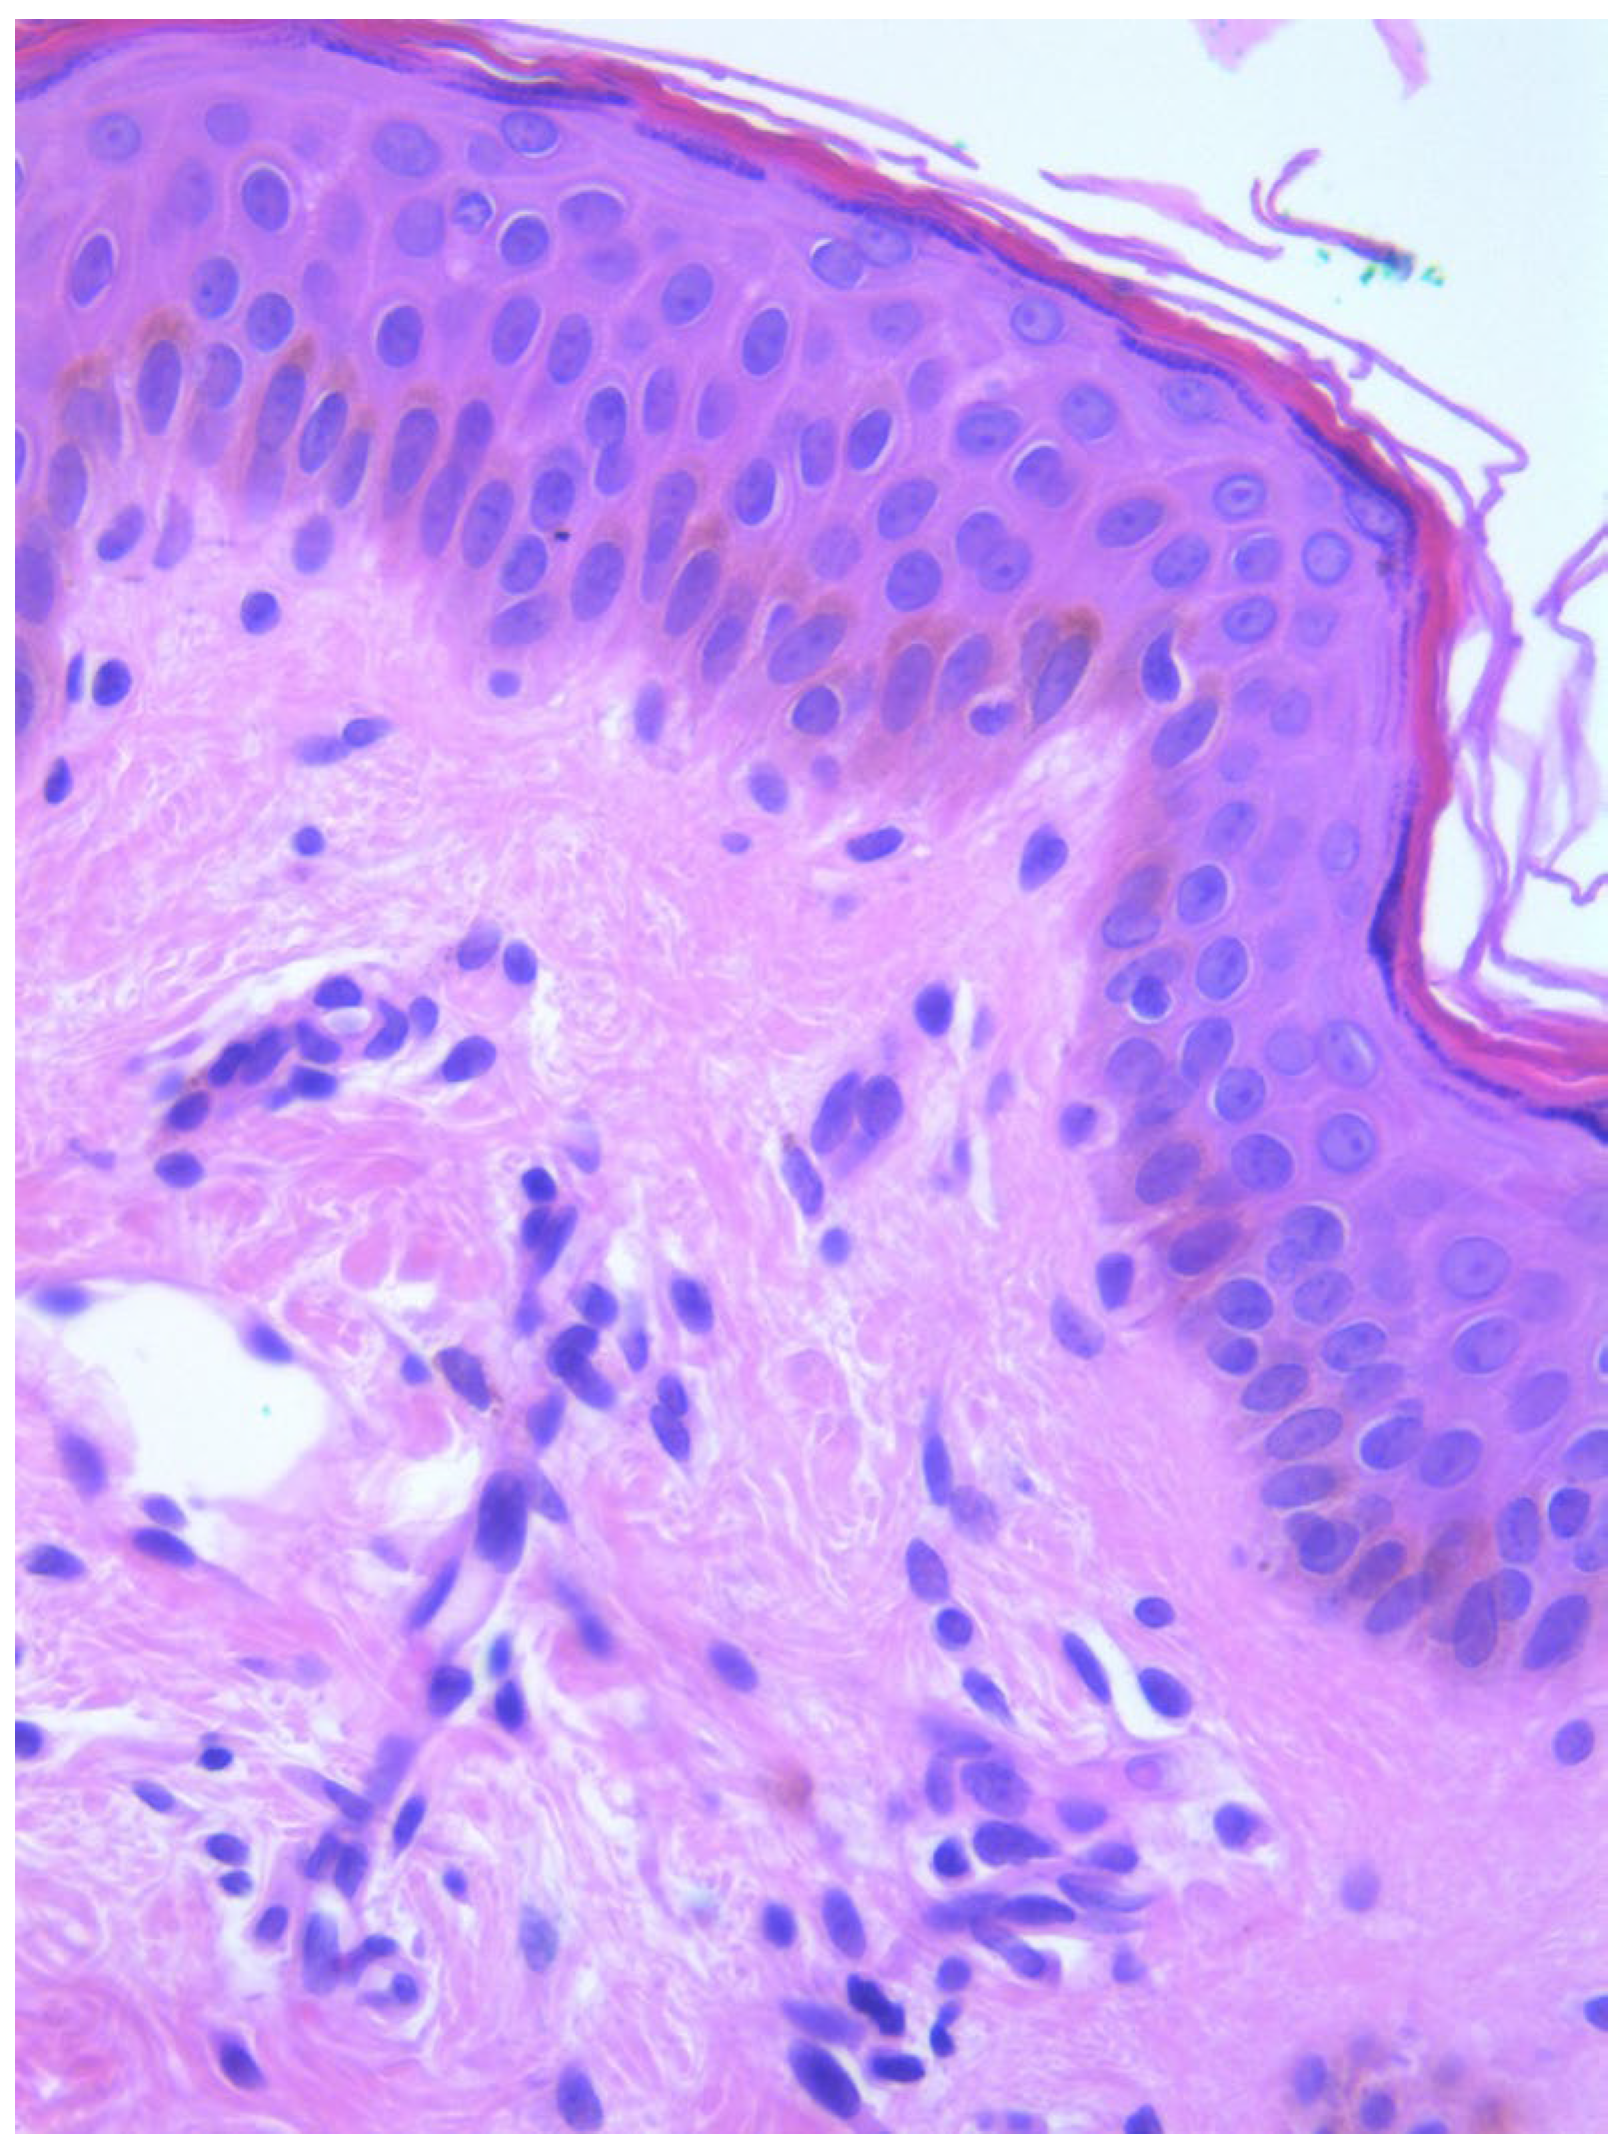

Two skin samples were taken from the upper and lower back, both showing slight, basal cell hyperpigmentation and an inflammatory infiltrate in the superficial dermis (Figure 3). Immunohistochemical stains with tryptase and CD117 showed that the infiltrate included mast cells (Figure 4), mostly with perivascular distribution. Mast cell count in six samples ranged from 11 to 12 mast cells per high-power view (CD117 and tryptase, respectively). The count per mm2 showed 34 mast cells with tryptase and 48 with CD117. C-kitD816V mutation analysis was not available. The bone scintigram did not detect any alterations and an abdominal ultrasound ruled out visceromegaly and only showed 10 mesenteric lymph nodes of non-specific appearance. He is currently under control and receiving oral levocetirizine 5 mg at night.

Figure 4. Mast cell infiltration (CD117, ×400).